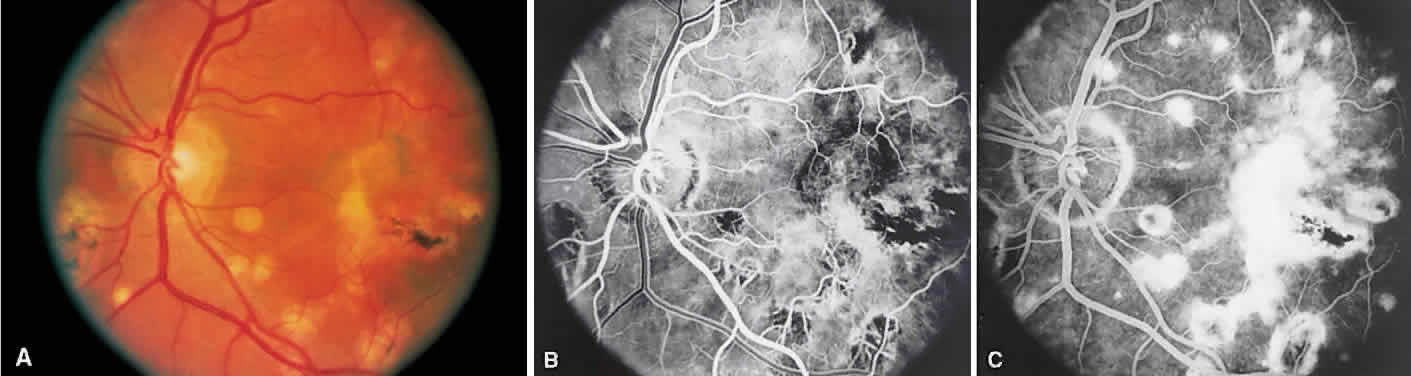

Behçet's disease is a systemic occlusive vasculitis that presents predominately in young middle Eastern and Japanese men. The classic features include acute hypopyon, iritis, aphthous stomatitis, and genital ulceration. Skin lesions and strokes also occur frequently. There often is an acute recurrent bilateral panuveitis. Ocular findings include retinal vasculitis (Fig. 6A) with an occlusive arteritis, vitritis, macular edema, ischemic retinitis, ischemic optic neuropathy, peripheral neovascularization, and occasionally SRNV.

Fig. 6. Behçet's disease. A. Fundus photograph showing vasculitis of the superotemporal vascular arcade. Intraretinal hemorrhages also are seen. B. Fluorescein staining of the vessel wall and adjacent areas of blocked fluorescence corresponding to the intraretinal hemorrhage.

On fluorescein angiography (see Fig. 6B), during the active phases of the disease, capillary dropout and dilated retinal capillaries are seen. Dilated retinal capillaries (particularly peripapillary capillaries) leak dye and cause retinal and disc staining.19 Cystoid macular edema,19 SRNV, and disciform scars often are seen.20 Leakage of peripheral capillaries can be seen in patients with normal-appearing fundi.21

ICG angiography shows hyperfluorescent spots from the early to late phases and hypofluorescent plaques, both of which are not evident on FA. Staining of choroidal vessel walls and leakage of ICG from the choroidal vessels also have been described.22–24

SARCOIDOSIS

Sarcoidosis is a systemic, idiopathic, noncaseating, granulomatous disease that affects various organs, including the eye, brain, lung, and skin. Ocular findings may include conjunctival nodules; anterior iridocyclitis; vitreous cells; retinal, optic nerve, and choroidal granulomas (Fig. 7A); retinal vasculitis (venules are preferentially affected); cystoid macular edema; retinal vessel occlusion; and disc and retinal neovascularization.

Fig. 7. Sarcoidosis. A. Choroidal granuloma. B. Fluorescein angiogram shows staining of the choroidal granuloma.

The FA reflects the various clinical entities. Retinal venular walls stain, particularly where there are perivenular exudates.25–27 More extensive venous involvement can produce a picture of dilated veins and perivenous leakage.27 Peripheral neovascularization occurs near areas of retinal capillary nonperfusion.25,28 Optic disc granulomas and optic disc neovascularization both leak extensively (Fig. 8A); sarcoid retinal lesions also stain (see Fig. 7B).27 In disc edema, the disc is hyperfluorescent and leaks fluorescein (see Fig. 8B).25

Fig. 8. Sarcoidosis. A. Fluorescein angiography shows two separate areas of neovascularization of the peripheral retina. B. Extreme leakage of dye from the right disc with cystoid macular edema of the right macular region in a patient with chronic sarcoidosis.

Four main patterns can be identified with ICG angiography. The first and most common pattern is hypofluorescent dark spots in the early and intermediate phases of the angiogram. These spots either become isofluorescent or remain hypofluorescent in the late phases. The second pattern is focal hyperfluorescent spots seen in the intermediate and late phases. The third pattern is fuzzy choroidal vessels due to perivascular choroidal leakage in the intermediate phase. Finally, the fourth pattern is characterized by diffuse zonal hyperfluorescence representing choroidal staining in the late phase of the angiogram. The latter two patterns resolved after systemic corticosteroid treatment.29